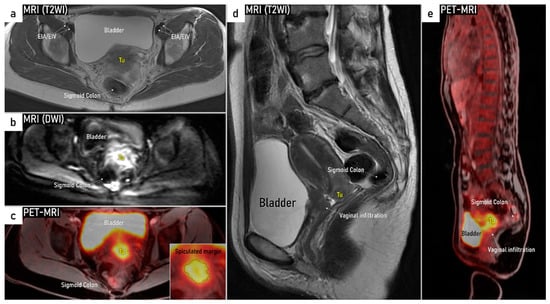

| T4 f | IVA f | Tumour invasion into the mucosa of the bladder or rectum (biopsy-proven) or into adjacent organs. | Tumour invasion into the mucosa of the bladder or rectum on imaging, confirmed by biopsy. US: Negative sliding sign, hypoechogenic tumour infiltration of bladder/rectal wall up to echogenic mucosa with polypoid tumour seen intraluminally. MRI: Focal or diffuse disruption of the normal T2-low signal intensity wall of the bladder/rectum, irregular or nodular wall, sometimes including an intraluminal tumour mass. Bulous edema sign, which is hyperintense thickening of the bladder mucosa on T2W images, is only an indirect sign of invasion and should not be regarded as T4 unless confirmed mucosal infiltration at cystoscopy. Infiltration of the posterior bladder wall without mucosal infiltration should not be regarded as T4a. |